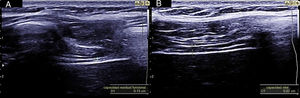

La medición del desplazamiento evalúa la capacidad del diafragma de generar cambios de volumen en la caja torácica. Se realiza un abordaje subcostal, usando una sonda convexa de baja frecuencia a nivel de la línea medio clavicular, buscando el tercio posterior de la cúpula diafragmática en el lado derecho, a través de la ventana hepática. En el lado izquierdo se utiliza la ventana esplénica, pero la cúpula es más difícil de localizar, especialmente si hay interposición de vísceras abdominales6. Una alternativa es el abordaje lateral, colocando la sonda en posición perpendicular en los espacios intercostales inferiores a nivel de la línea medio axilar. Tras la localización de la cúpula en «modo 2D», el modo ecográfico «M anatómico» facilita la identificación de la porción de la cúpula con mayor movilidad, para su medición en un corte sagital. Se mide el desplazamiento en respiración en reposo (volumen corriente), en inspiración y espiración profundas (capacidad vital) o en maniobras de sniff (fig. 1). Puede medirse también su potencia (desplazamiento a lo largo del tiempo, en forma de pendiente de la curva de desplazamiento). En algunas situaciones en las que no se discrimina adecuadamente el diafragma, se puede medir el desplazamiento de vísceras abdominales (vena cava en el lado derecho, o del bazo en el izquierdo), con aceptables resultados. Esto se conoce como «método indirecto»7.

La medición del grosor diafragmático es otro método actualmente empleado, permite determinar la masa muscular diafragmática, y valorar la fracción de engrosamiento, o «thickening fraction» (TF). Para esta medición se utiliza una sonda lineal de alta frecuencia, colocada entre los últimos espacios intercostales. De esta forma se localiza la «zona de aposición», donde el diafragma se inserta en la pared costal. El diafragma se identifica como la franja hipoecogénica limitada por dos líneas hiperrefringentes, que corresponden a la pleura y al peritoneo. El TF es la relación entre el grosor en reposo (capacidad residual funcional) y en máxima inspiración (capacidad vital) (figs. 1 y 2).